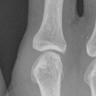

Patient 403 has erosion '5' on his right "pointing finger"

However.. that one looks fine to me.

Right (5 label)